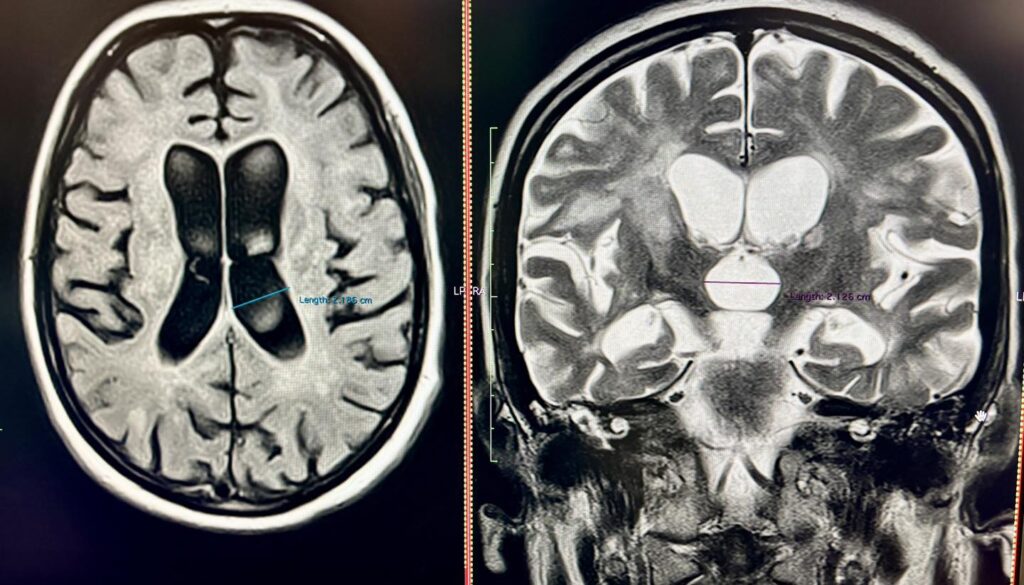

40-річна Соломія не могла самостійно дихати, їсти, розмовляти та ходити. Саме у такому стані вона потрапила у приймальне відділення Університетської лікарні. З 2018 року Соломія страждає на розсіяний склероз, але жодного разу не лікувала це захворювання. Коли вона вже була без свідомості, мама викликала “швидку”

Замість Соломії дихав апарат ШВЛ, замість повноцінної їжі вона отримувала спеціальне харчування через назогастральний зонд. Крім неврологічних проблем, у пацієнтки діагностували важке токсичне ураження печінки, тромбоемболію легеневих артерій, тромбофлебіт (запалення стінок вен і формування тромбу у судині) у нозі і запалення вуха.

За 20 днів лікування у Клініці неврології та нейрохірургії Університетської лікарні Соломія буквально ожила – повернулася до свідомості, знову може ковтати і їсти, розмовляє, самостійно дихає і вже робить перші кроки.